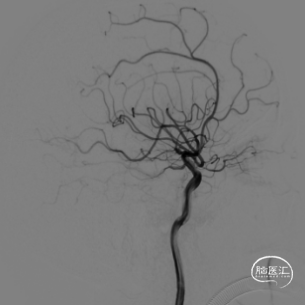

动脉瘤虽然比较小,但是由于瘤颈只有1mm,动脉瘤又起源于前动脉A1段后壁,使瘤颈开口与颈内动脉之间形成一个较大的锐角弯,因此微导丝超选困难,弹簧圈微导管置入后稳定困难,经反复尝试,最终完全栓塞。

术后患者一般情况良好。